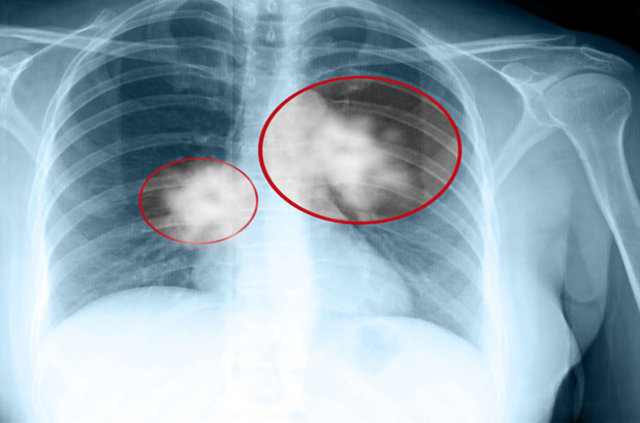

Bu tümörler, erken dönemlerde yıllar boyunca belirgin bir şikâyete neden olmadan sinsi bir şekilde kalabilir. Hastalık ilerleyince en sık görülen şikayetler geçmeyen öksürük, kan tükürme, halsizlik, iştahsızlık ve kilo kaybıdır.”

“Akciğer kanserlerinin yüzde 5'i erken evrede yakalanırsa tama yakın tedavi edilebilir. Geri kalanlarda ise yapılan tedavilerle hastalıksız dönemin uzatılması hedeflenir.